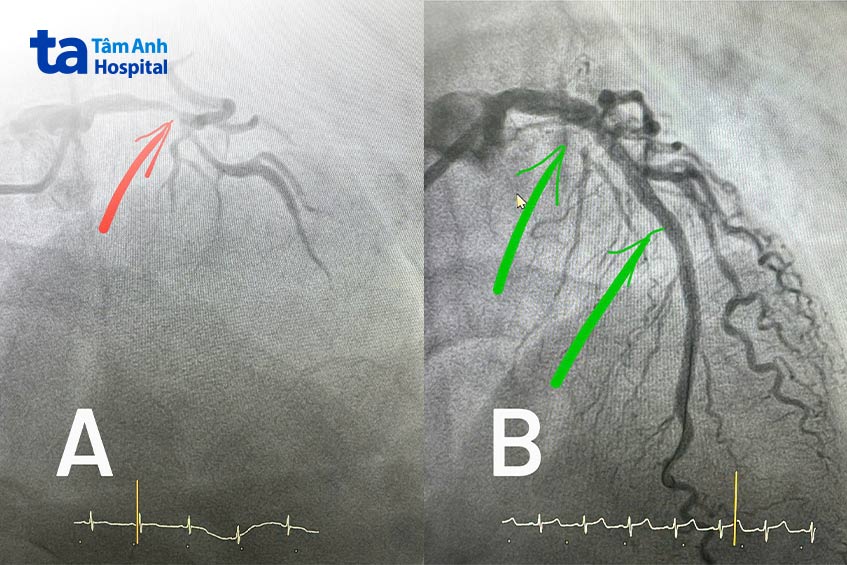

Bác sĩ chỉ định chụp mạch vành, xác định thân chung mạch vành trái hẹp 90-95%, động mạch liên thất trước hẹp lan tỏa 95%. Đây chính là nguyên nhân gây chậm dòng chảy, khiến lưu lượng máu nuôi tim giảm nghiêm trọng, dọa nhồi máu cơ tim nếu không nong mạch tái thông kịp thời.

Ngoài ra, bệnh nhân còn đối mặt nguy cơ nhồi máu cơ tim nếu can thiệp đặt stent theo cách thông thường. “Thao tác luồn dây dẫn nong bóng từ một nhánh đến thân chung rất dễ tạo ra lực đè ép nhánh bên còn lại. Hệ quả là thân chung được nong nhưng nhánh bên lại tắc”, bác sĩ Minh nói. Để khắc phục, ê kíp áp dụng kỹ thuật kissing balloon. Thông qua một ống thông chung, hai dây dẫn gắn bóng được đưa vào hai nhánh mạch vành trái, sau đó nong đồng thời hai nhánh này, tránh tình trạng chỉ nong một nhánh gây đè ép nhánh bên.

Bác sĩ lựa chọn loại dây dẫn phù hợp, không quá mềm (vì khó đi qua chỗ mạch vành hẹp), không quá cứng (dễ gây xé vách thành mạch). Dưới hướng dẫn của hệ thống siêu âm trong lòng mạch vành – IVUS, trong vòng 40 phút, bác sĩ đặt stent kéo dài từ động mạch liên thất trước lên thân chung mạch vành, tạo hình lại chỗ chia đôi. Nhờ vậy, bệnh nhân không gặp biến chứng rối loạn nhịp tim, suy tim, thủng mạch vành trong quá trình can thiệp.

Siêu âm trong lòng mạch thấy các đoạn mạch tắc hẹp được mở rộng, nguồn máu cung cấp cho tim được khôi phục, stent nở đều áp sát thành mạch. Ông Mạnh hết hẳn đau ngực, đi lại bình thường chỉ vài giờ sau thủ thuật. Bệnh nhân xuất viện 2 ngày sau đó.